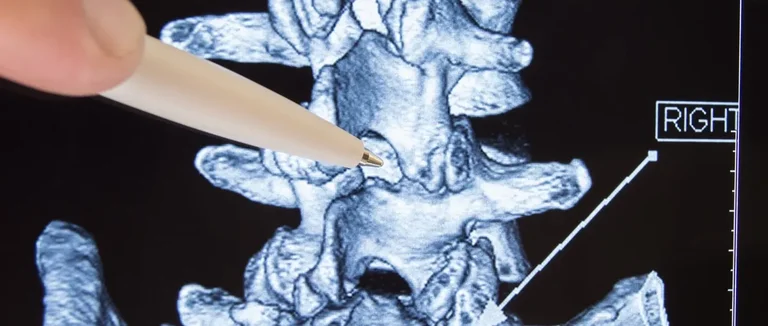

diagnostic par imagerie

diagnostic par imagerie médicale